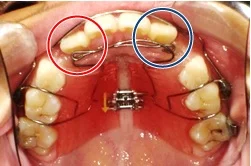

取り外し式拡大装置の症例

| 期間 | 6ヶ月(途中経過) |

|---|---|

| 種類 | 下顎拡大装置+MBS(2×4) |

| 費用 | 基本装置¥200,000(税込¥220,000)+調整料¥5,000(税込¥5,500)/回 |